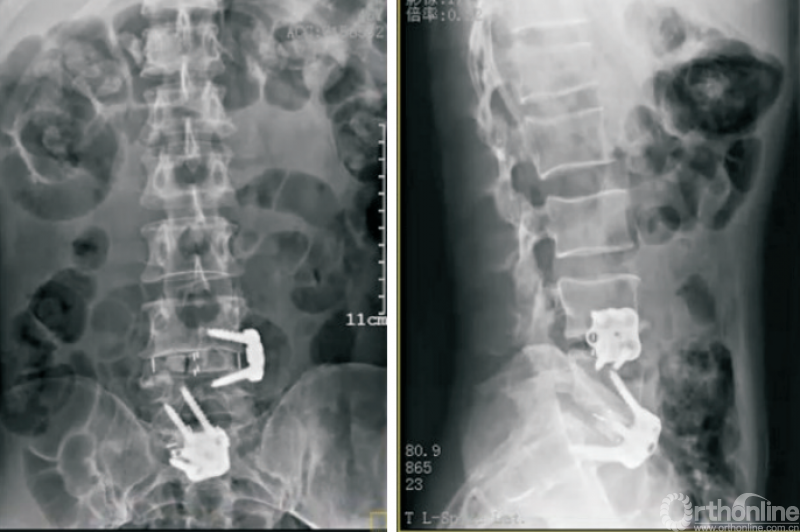

因此,侧方钢板的应用能部分解决这个问题[43]。斜外侧脊柱融合固定系统(PIVOX)(图7)是目前比较成熟的侧方固定方式,已在我科初步应用,用于腰椎节段性不稳定、腰椎椎管狭窄、腰椎侧弯、腰椎盘源性腰痛、邻椎病(图7)等腰椎疾病,截至目前随访结果满意。

图7 PIVOX系统用于邻椎病

初步统计结果显示,相较于经典的OLIF组,PIVOX组并未明显增加融合器沉降、终板塌陷等并发症的发生率。在发挥Stand-alone OLIF优势的同时,保证了脊柱生物力学的稳定性,拓展了Stand-alone OLIF的应用边界。但是,NAYAK等[44]的研究发现,对于侧方脊柱融合术,后路螺钉固定的生物力学稳定性强于侧方钢板固定,因此,当需要刚性、消除运动的稳定时,仍然建议首选后路螺钉固定。